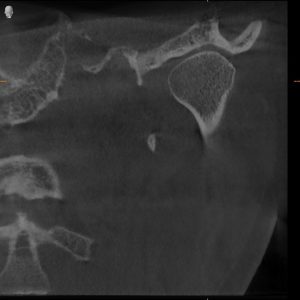

MRI Findings:

- Bilateral disc displacement without reduction

- This explained everything — the pain, the restriction, the dysfunction